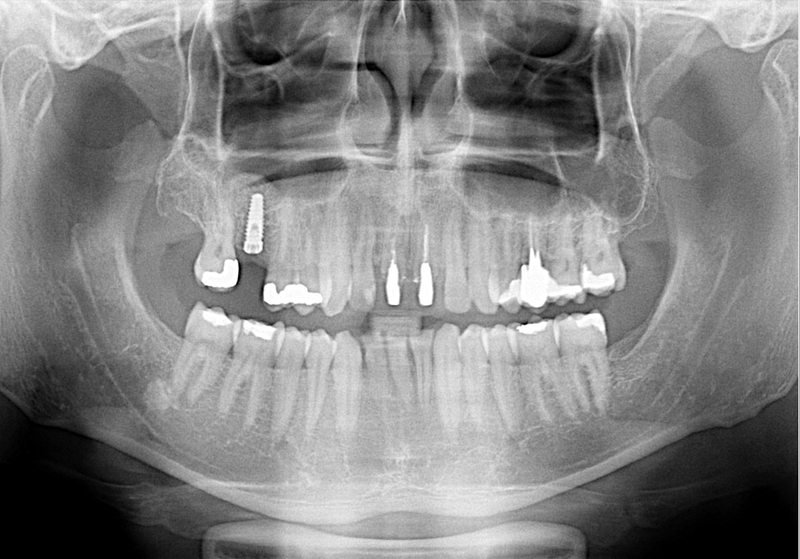

Nejčastější oblastí pro doplnění kosti je čeleni dutina horní čelisti.

Tento výkon se nazývá sinus lift - aplikace kostního granulátu do čelistní dutiny

Při ztrátě molárů a premolárů v horní čelisti a jejich náhradě implantáty se často setkáváme s nedostatečnou vertikální nabídkou kosti pod čelistní dutinou, často doprovázenou i nedostatečnou horizontální nabídkou a sníženou kvalitou kosti

(v oblasti 2. premoláru v 50%, v oblasti moláru až v 80% případů nedostatečná kostní nabídka)

Od roku 1985 je tento problém řešen augmentační operací nazývanou sinus lift.

Jedná se o vyzvednutí membrány, která čelistní dutinu vystýlá, pod vyzvednutou membránou vznikne kapsa, kam se umístí augmentační materiál, do kterého se zavedou implantáty.

Vhojení implantátů se při této operaci prodlužuje na 6-12 měsíců.